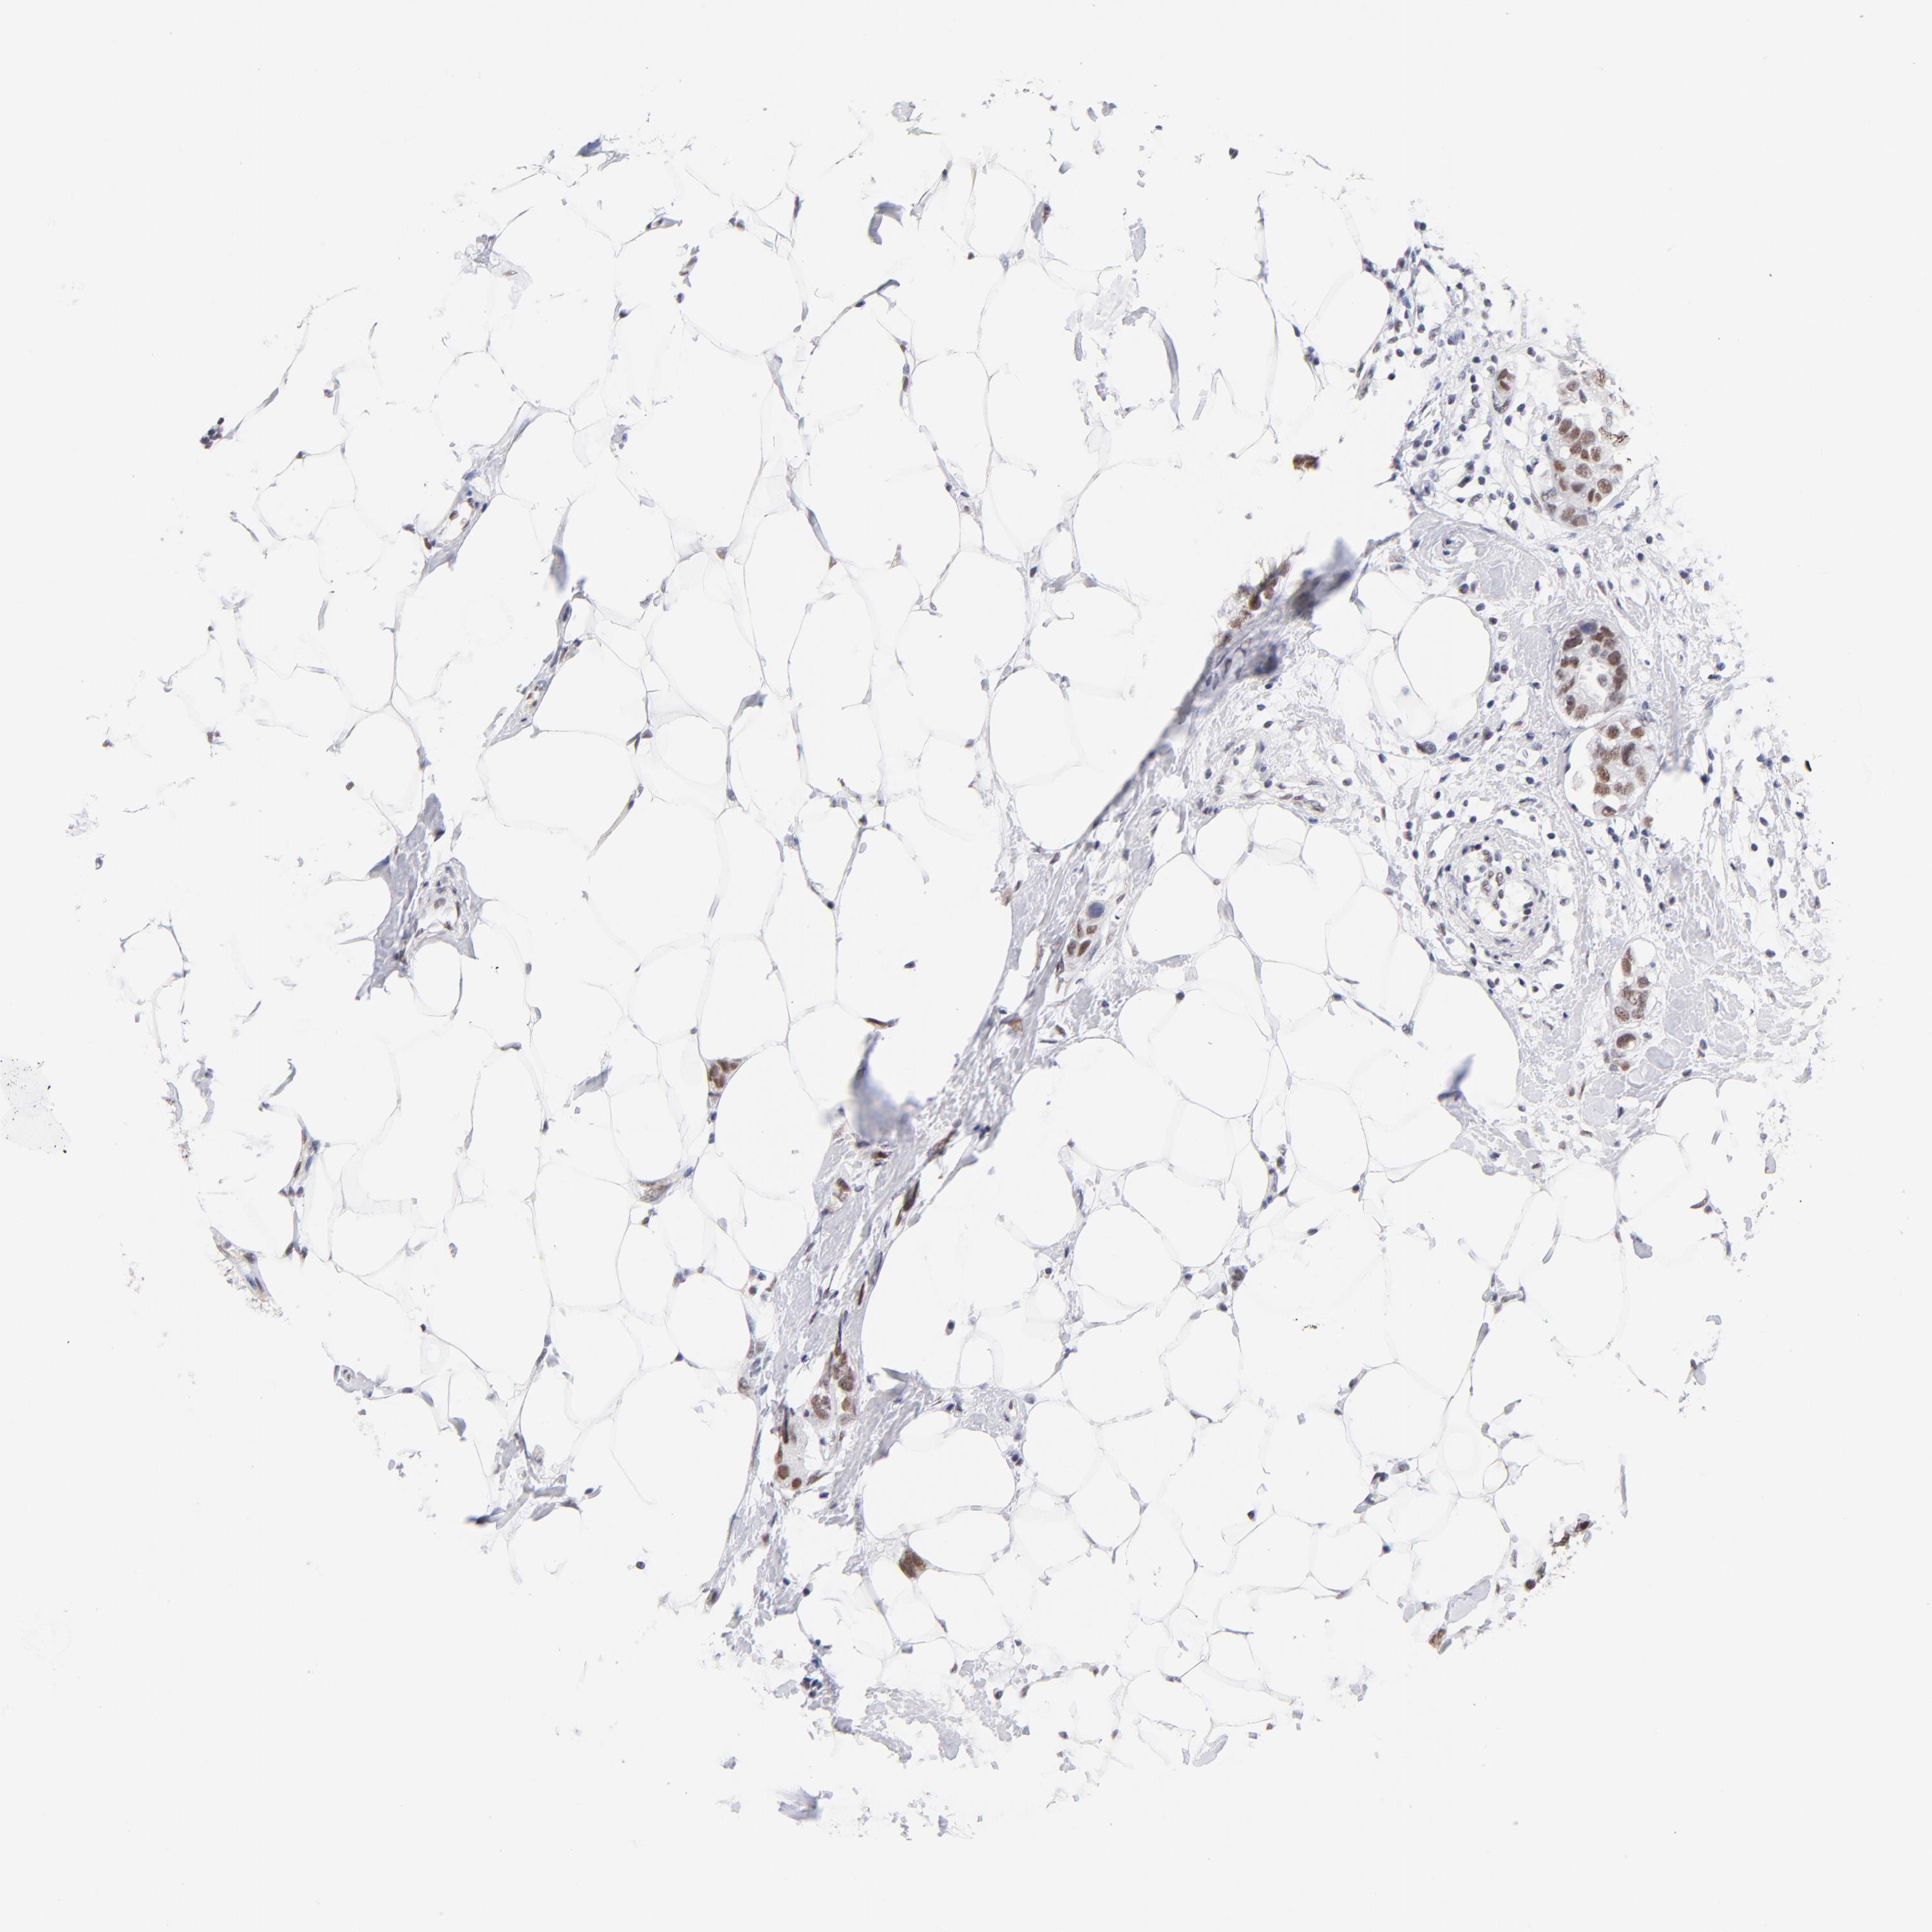

BRCA TCGA BRCA VALIDATION PROTEIN EXPRESSION

ANTIBODIES

AND

VALIDATION